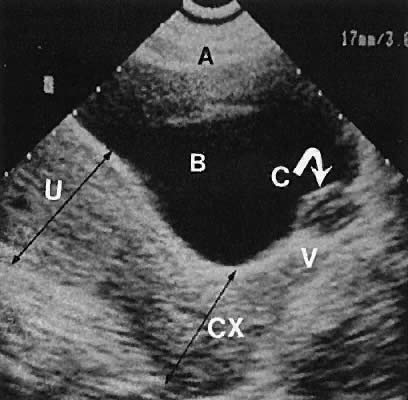

Fig. 21. Longitudinal transabdominal scan depicting a Gartner duct cyst (a mesonephric duct remnant). C, cyst in vaginal wall; V, vagina; U, uterine fundus; CX, cervix; B, bladder; A, near-field reverberation artifact.